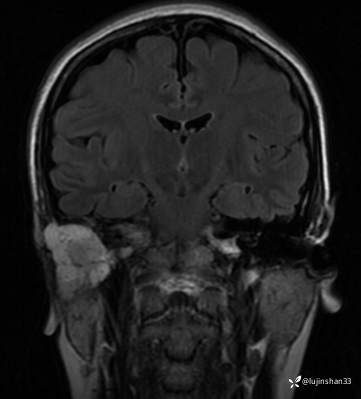

颞骨MRI:

临床诊断:1.右侧岩部胆脂瘤 2.外耳道耵聍癌术后(右)